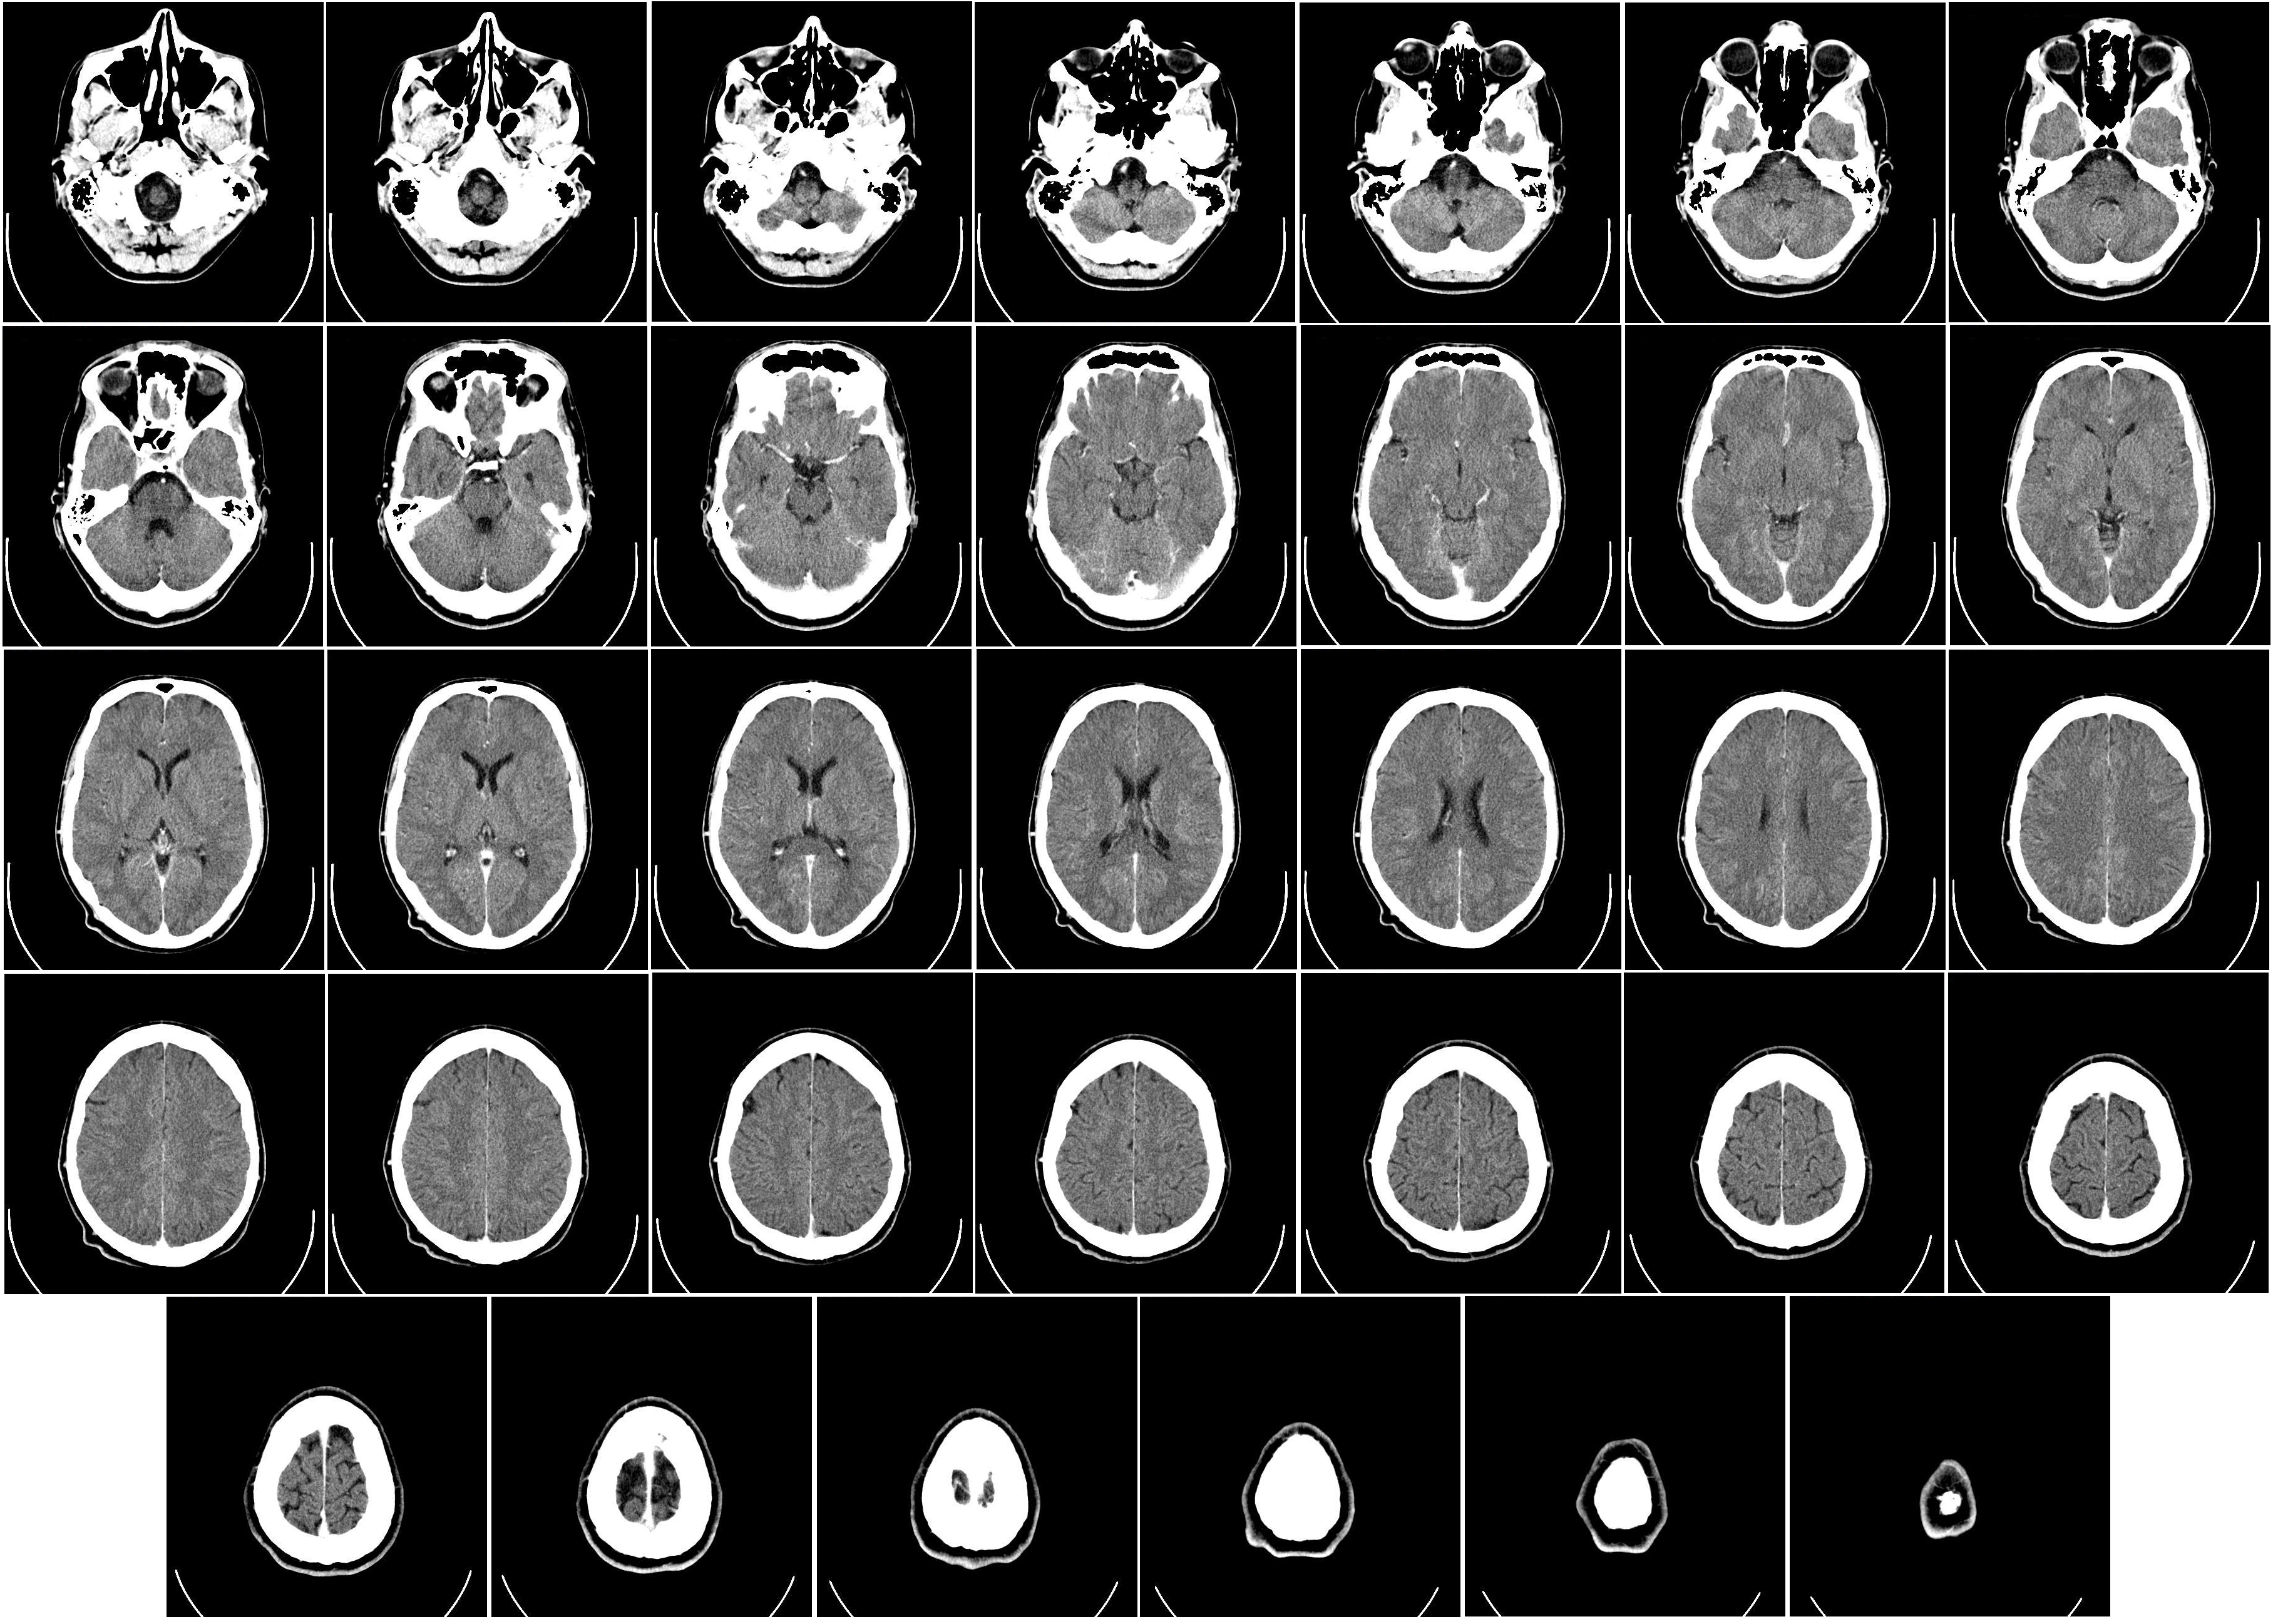

CAT

Computer Aided Tomography / CT

A process that uses a series of x-ray scans to the head in order to reconstruct 2D x-ray images into 3D images of internal organs; The subject enters a donut-shaped x-ray machine

Measures Tissue Density by X-Ray

Very dense tissue (e.g. Bone) blocks x-rays, so it appears white on the scan

Grey matter blocks some x-rays, so it appears light grey

White matter blocks less x-rays, so it appears dark grey

The images produced are not as detailed as MRI scans and there is some radiation, but these scans are cheaper than MRI

Provides an image for the STRUCTURE of the brain